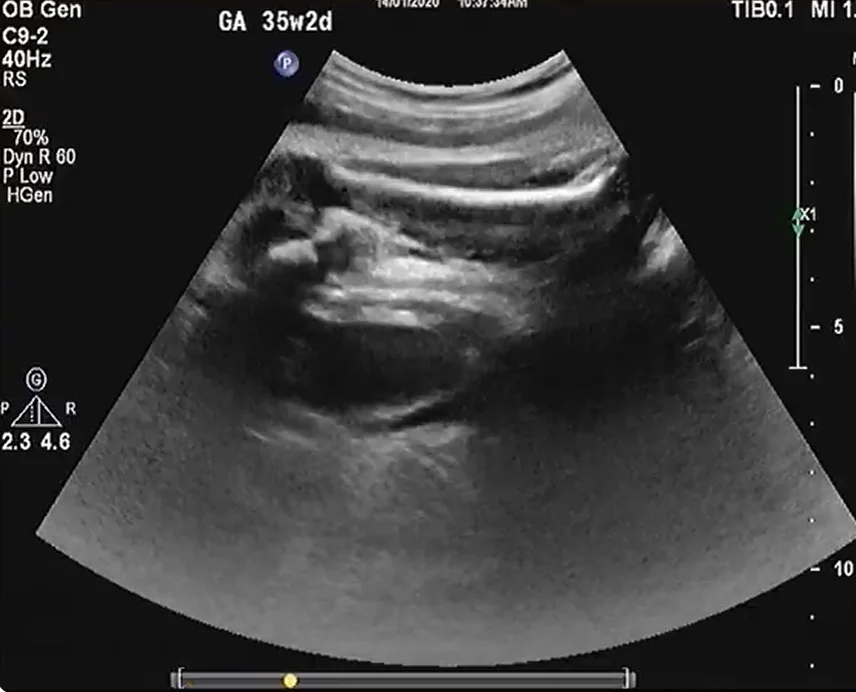

Bất sản thận một bên (Unilateral Renal Agenesis)

Thận móng ngựa thai nhi (Horseshoe Kidney)

Thận lạc chỗ bắt chéo dính nhau ở thai (Crossed fused renal ectopia)

• Các biến thể phát triển của thận

• Bất sản thận một bên (Unilateral Renal Agenesis)

• Thận móng ngựa thai nhi (Horseshoe Kidney)

• Thận lạc chỗ bắt chéo dính nhau ở thai (Crossed fused renal ectopia)